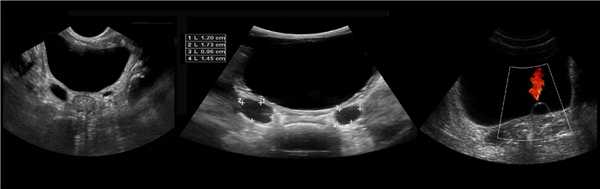

Рисунок. На УЗИ расширенный дистальный отдел мочеточника (1, 2, 3). Про уретероцеле (3) подробнее смотри здесь.

Рисунок. На УЗИ округлое образование разделяет почечный синус на два сегмента с общей лоханкой; междолевые артерии огибают образование; эхогенность и интенсивность сосудистого рисунка внутри близка корковой зоне. Заключение: Гипертрофия колонны Бертини или неполная паренхиматозная перемычка. Это вариант нормального строения почки. Термин «неполное удвоение ЧЛК» неверный, т.к. неполная паренхиматозная перемычка не является признаком удвоения ЧЛК.

Рисунок. На УЗИ синус почки разделяет полная паренхиматозная перемычка (1, 2). В таких случаях разграничить удвоение почки от гипертрофии колонны Бертини поможет экскреторная урография. Удвоенная почка покрыта общей фиброзной капсулой. Полное удвоение предполагает наличие двух лоханок, двух мочеточников и двух сосудистых пучков. Неполноудвоенная почка (3) питается одним сосудистым пучком, мочеточник может быть удвоен вверху и впадать в мочевой пузырь одним или двумя устьями. Удвоение ЧЛК и мочеточников — фактор риска развития патологии (пиелонефрита, гидронефроза и др.).